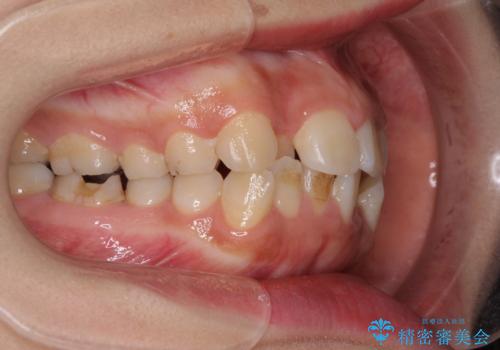

- 前歯のデコボコと上顎の前突感による口の閉じにくさを気にして来院された患者様です。

目立たない装置を希望されたので、上顎が裏側装置のハーフリンガルを選択し、上下左右の小臼歯(計4歯)を抜歯して矯正治療を行うこととしました。

また、左下の奥歯は抜歯が必要な歯であったため、矯正治療中の良いタイミングで抜歯とインプラント埋入を行い、矯正治療後にオールセラミッククラウンで補綴治療を行うこととしました。

デコボコの解消までは非常にスムーズでしたが、咬合力が強いためか、スペースを閉じるまでに長い期間を要しました。

矯正治療途中にインプラント埋入と仮歯の装着を行ったことで、しっかりとした奥歯の咬み合わせで終了させることができました。